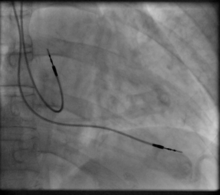

The first use of transvenous pacing in conjunction with an implanted pacemaker was by Parsonnet in the USA,[14][15][16] Lagergren in Sweden[17][18] and Jean-Jacques Welti in France[19] in 1962–63. The transvenous, or pervenous, procedure involved incision of a vein into which was inserted the catheter electrode lead under fluoroscopic guidance, until it was lodged within the trabeculae of the right ventricle. This method was to become the method of choice by the mid-1960s.

Transvenous pacing, when used for temporary pacing, is an alternative to transcutaneous pacing. A pacemaker wire is placed into a vein, under sterile conditions, and then passed into either the right atrium or right ventricle. The pacing wire is then connected to an external pacemaker outside the body. Transvenous pacing is often used as a bridge to permanent pacemaker placement. It can be kept in place until a permanent pacemaker is implanted or until there is no longer a need for a pacemaker and then it is removed.

Permanent pacing with an implantable pacemaker involves transvenous placement of one or more pacing electrodes within a chamber, or chambers, of the heart, while the pacemaker is implanted inside the skin under the clavicle. The procedure is performed by incision of a suitable vein into which the electrode lead is inserted and passed along the vein, through the valve of the heart, until positioned in the chamber. The procedure is facilitated by fluoroscopy which enables the physician to view the passage of the electrode lead. After satisfactory lodgement of the electrode is confirmed, the opposite end of the electrode lead is connected to the pacemaker generator.